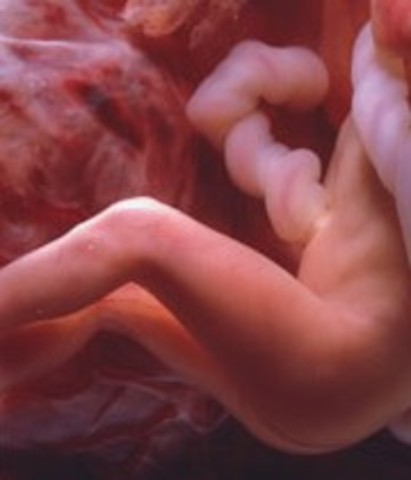

• Week Nine

Week Nine

The arms and legs have lengthened. Their fingers and toes are forming, but are webbed.

• Week Ten

Week Ten

From this week until birth, the embryo is called a fetus. The fetus is about the size of a strawberry. During this week, the fetus's fingerprints will form and the mouth and nose join.